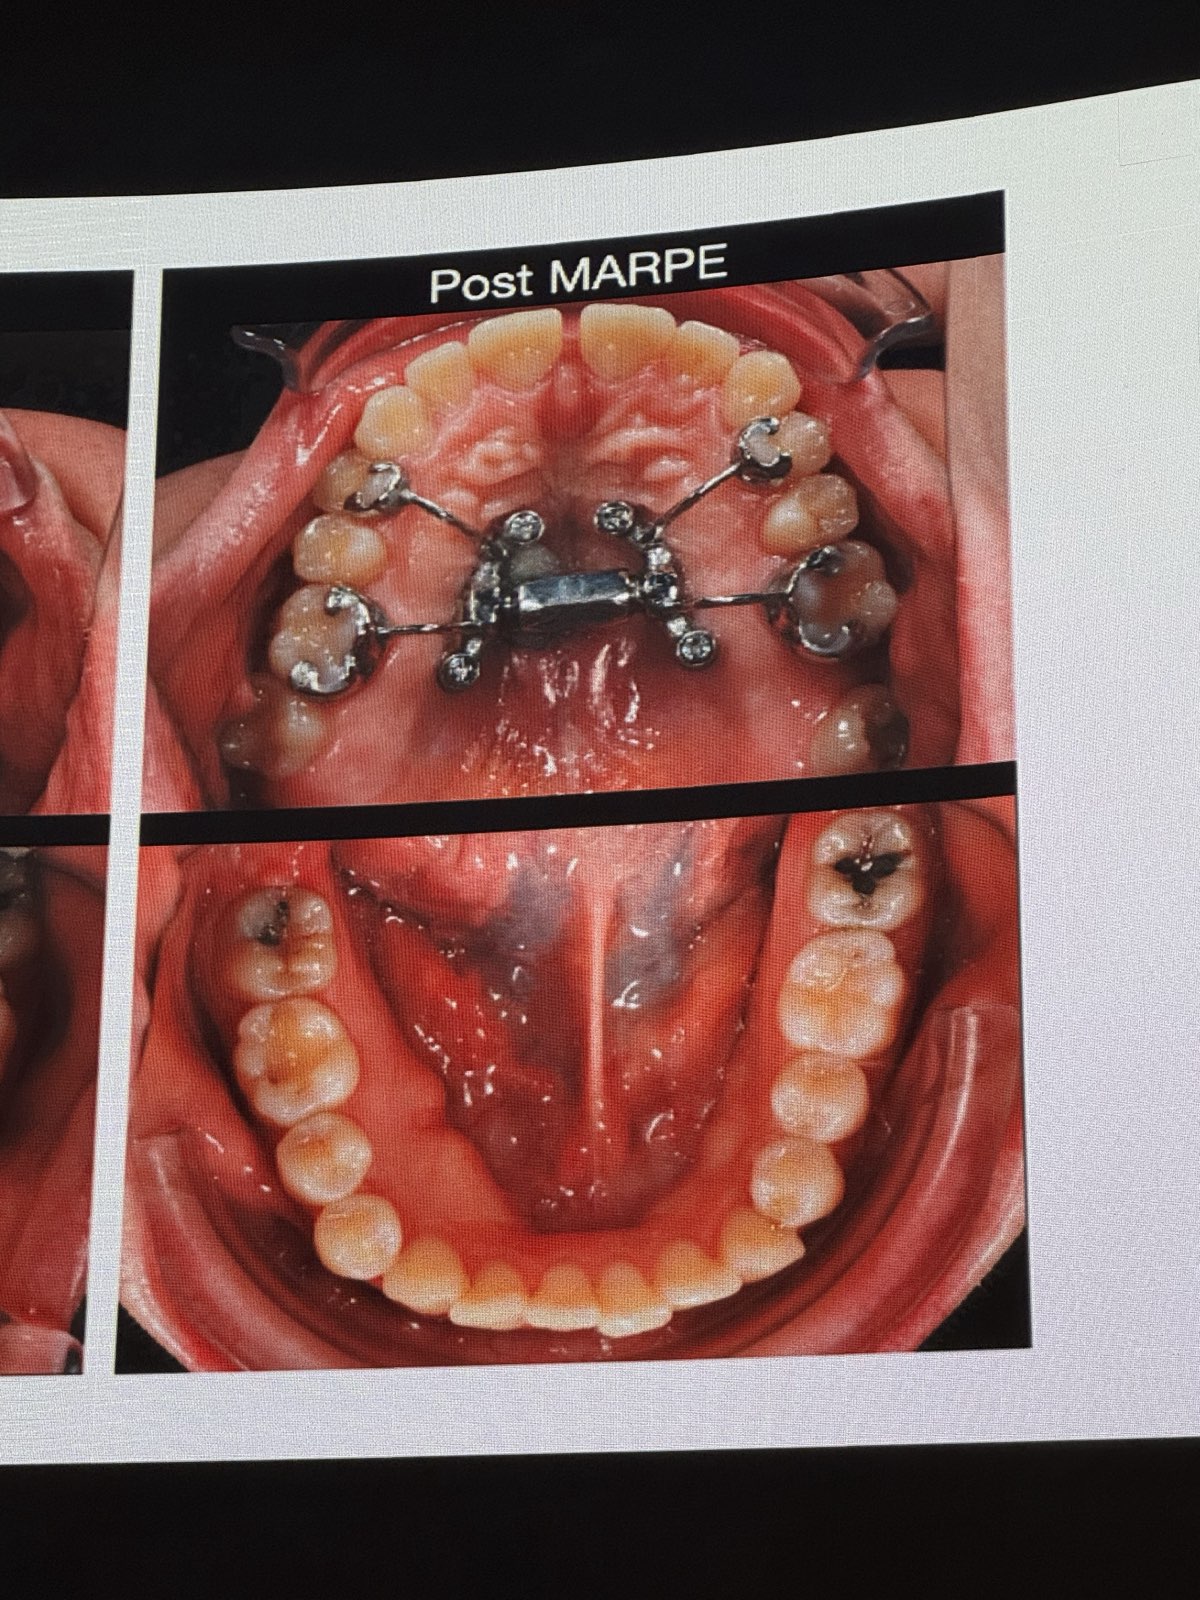

• MARPE(上顎急速拡大装置)に関する言及

• 重度横幅狭窄のある成人患者には、パワーネジ(Power Screw, ドイツTiger社製)のような強力なスクリューと、必要に応じて骨切り手術(ピエゾサージェリーシステムによる単純な手術)を併用したMARPEを適用する。

• 骨切り手術: 口蓋側のmaxillaに2つの小さな切開を入れ、ピエゾサージェリーの角度付きチップで縫合線を破断。切歯間にも切開を入れる。

• 効果: MARPEは骨格性の拡大を可能にし、歯の傾斜を防ぎ、成人における難症例の拡大をより予測可能にする。

• Tippingの制御: アライナーのずれを防ぐため、長方形の水平アタッチメントを配置することが有効。